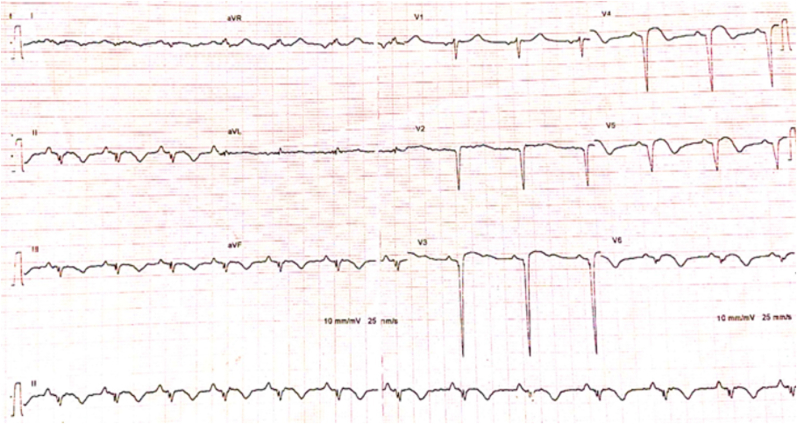

A 27-year-old patient, heavy smoker, long-term cannabis user (for 12 years), and occasional alcohol user. He doesn’t have any other risk factors for ischemic heart disease. He denied any other illicit substance abuse, including cocaine. The patient was referred to our department for post-myocardial infarction in the anterior and inferior leads. He reported prolonged chest pain one week before his admission, after cannabis smoking. Physical examination shows a heart rate at 94 bpm, blood pressure at 130/70 mmHg, a temperature of 36.2 C, a respiratory rate of 18 c/m and, and an oxygen saturation of 97%. The cardiac examination showed normal heart auscultation with discrete inferior limb edema. An electrocardiogram (EKG) revealed ST elevation on the anterior and the inferior leads with negative T waves and Q wave necrosis on the same territory (Fig. 1).